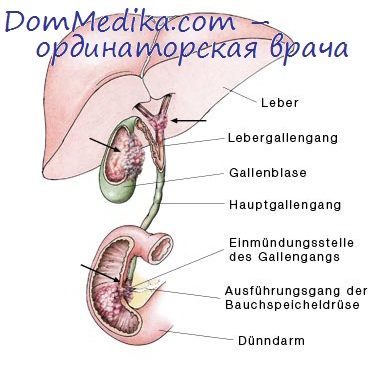

Анатомия и особенности Гартманова кармана желчного пузыря